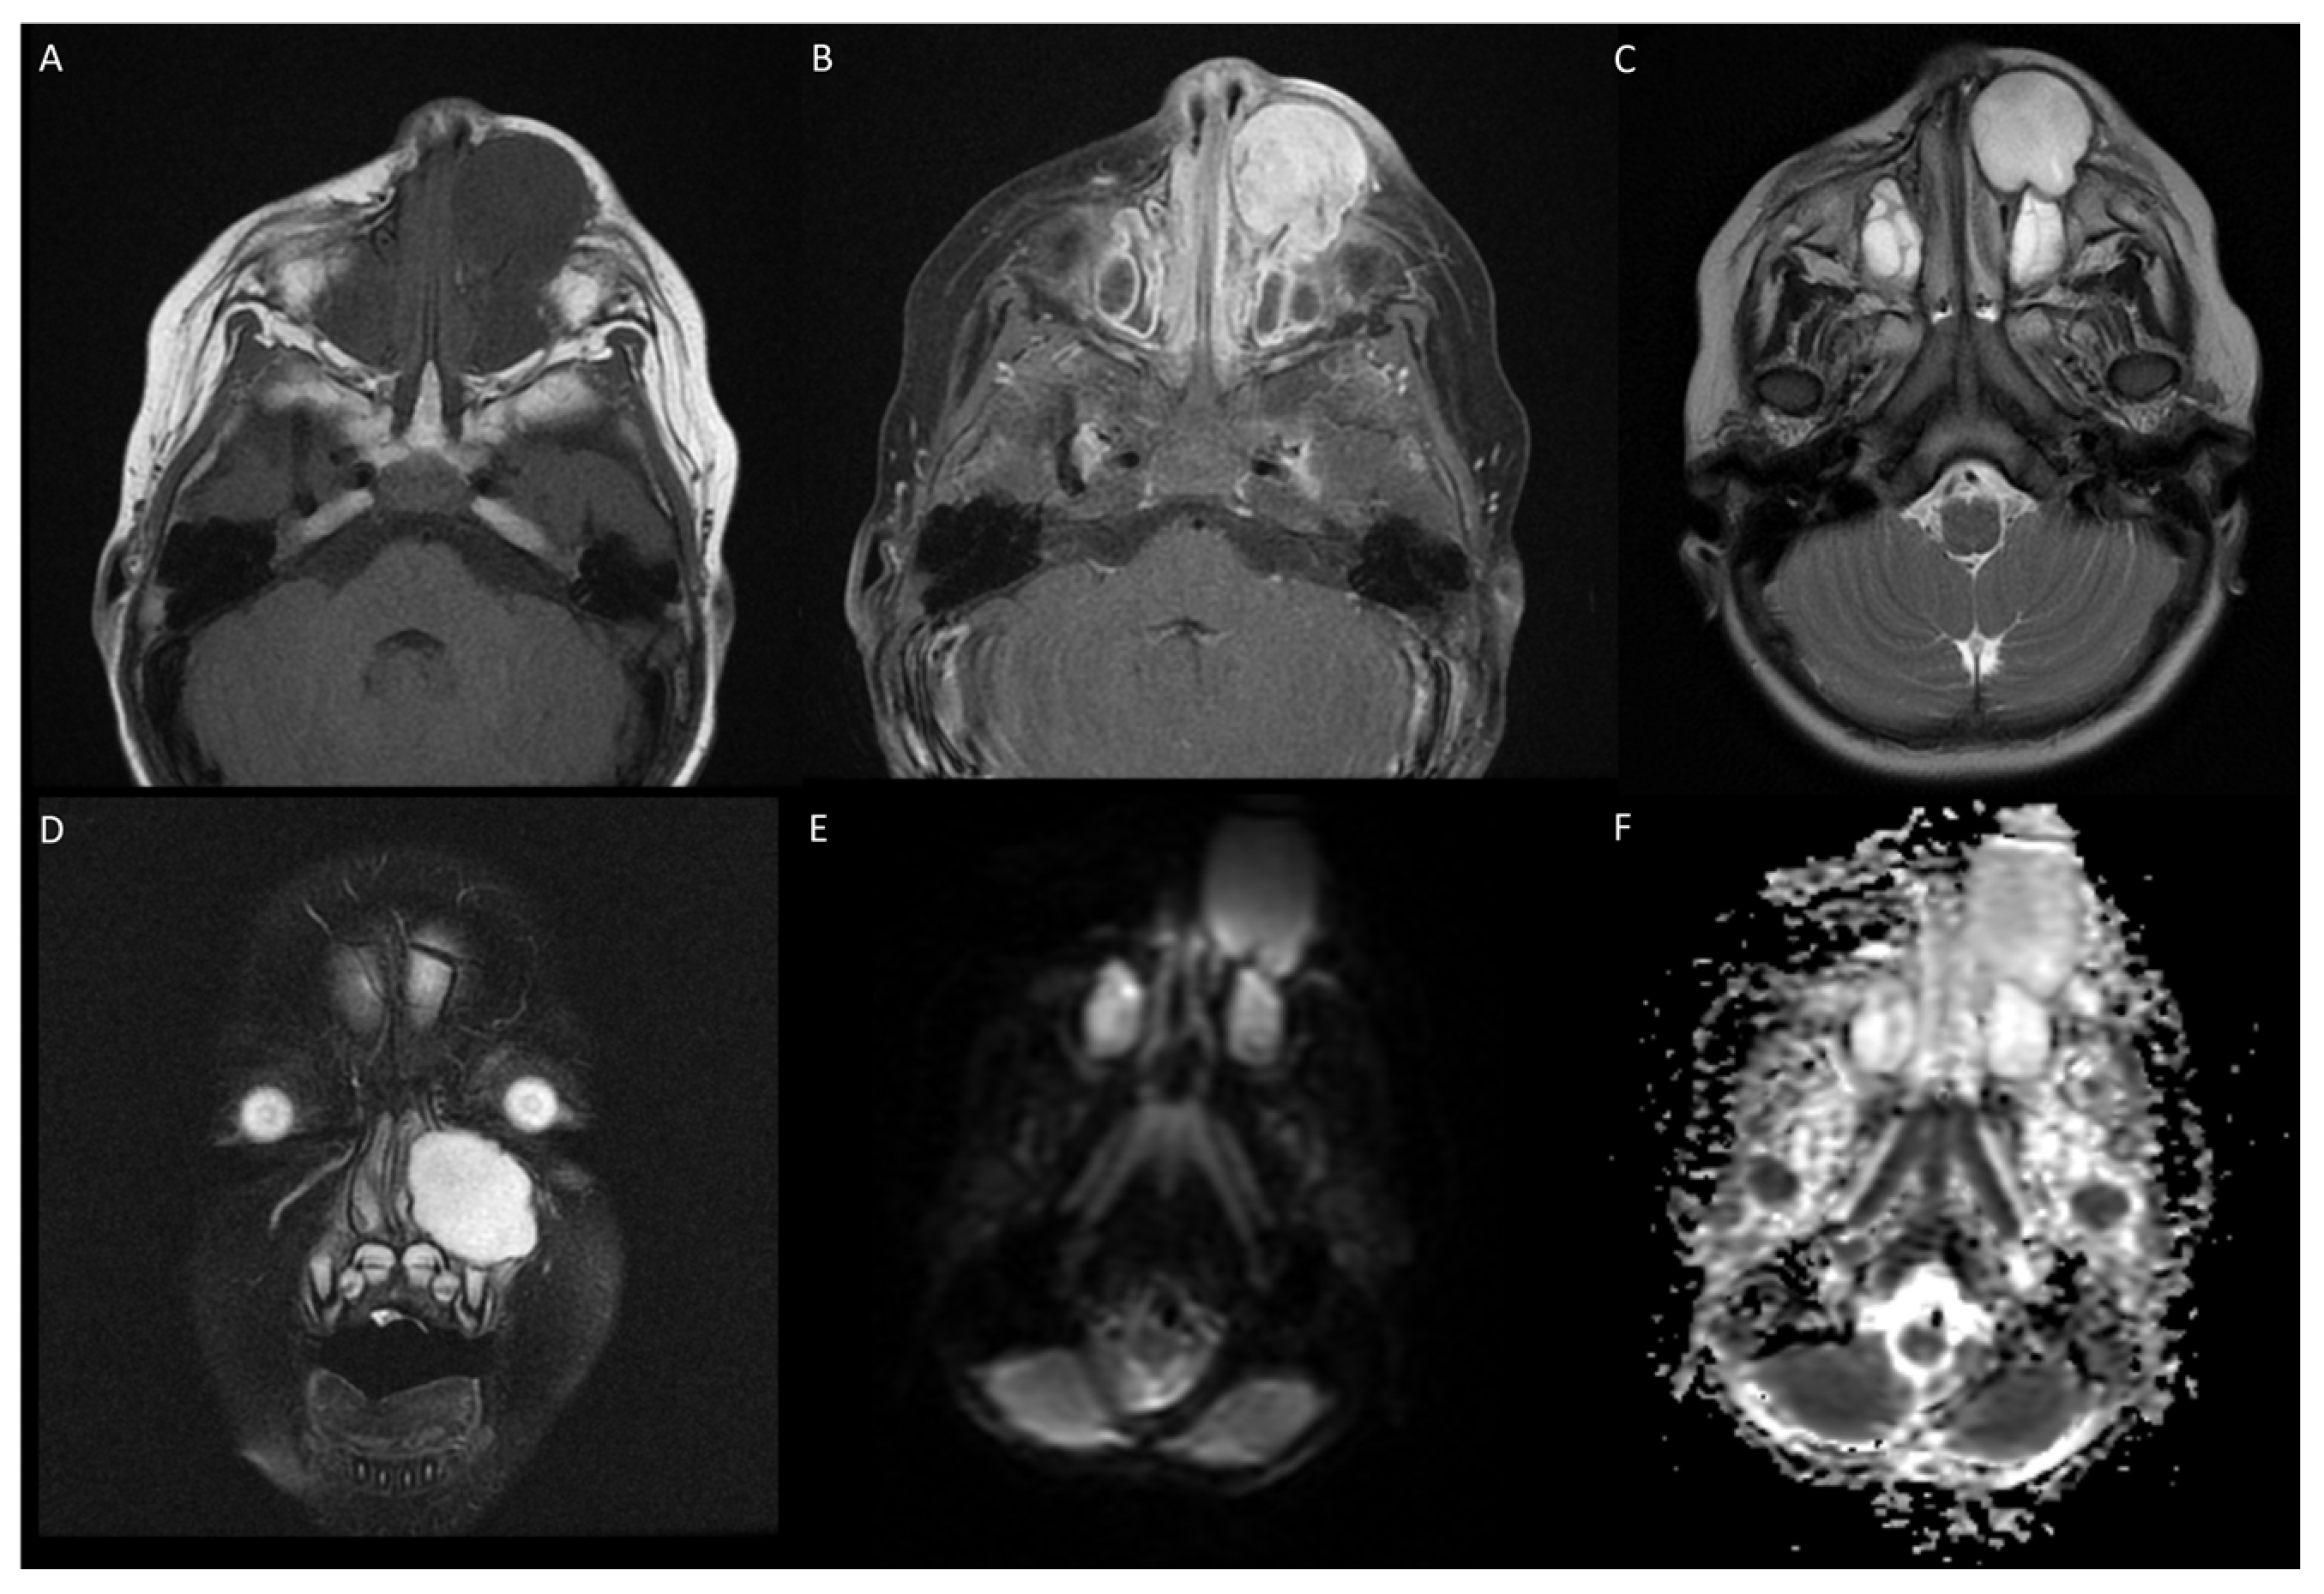

3.1. Case 1

3.2. Case 2